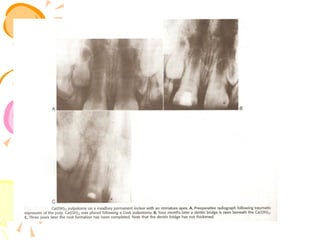

.Maturation of permanent incisors

a) Immature incisors showing short )

roots with incomplete, wide-open

apices. The lateral walls of the roots

. are thin and structurally weak

b) The same teeth 2 years later,)

the roots are now almost complete

following continued dentine

.deposition by healthy pulp